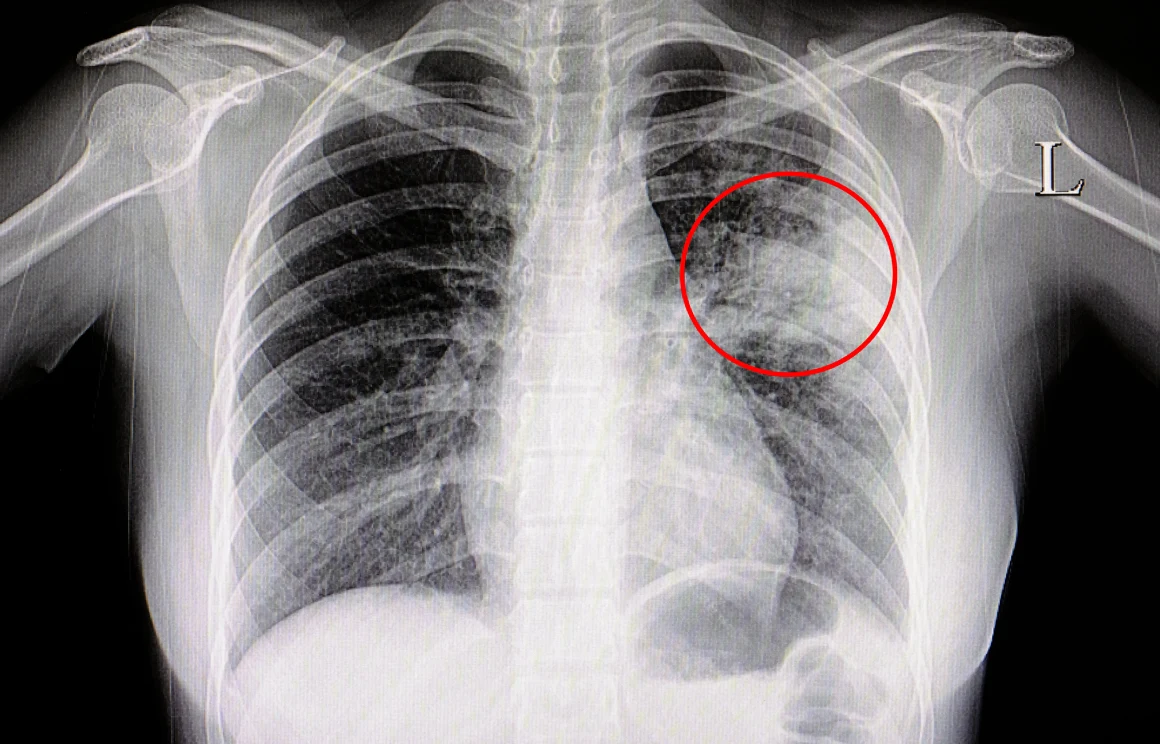

Lekarz przeprowadza wywiad z pacjentem i dokładnie go osłuchuje. W płucach chorego można spodziewać się obecności rzężeń i wyraźnych trzeszczeń. Czasami podejmuje się decyzję o wykonaniu badań obrazowych, zwłaszcza RTG, które ukazuje charakterystyczne zaciemnienie zajętych obszarów miąższu płucnego, czasami konieczne okazuje się zlecenie tomografii komputerowej, która jest badaniem dokładniejszym. Wskaźnikiem świadczącym o toczącym się zapaleniu jest stężenie białka CRP w krwi. Zdarza się, że trzeba wykonać bronchoskopię, która bez wątpienia jest badaniem nieprzyjemnym. Polega na endoskopowym pobraniu materiału biologicznego z dróg oddechowych. Próbkę można zbadać i w ten sposób poznać czynnik chorobotwórczy.